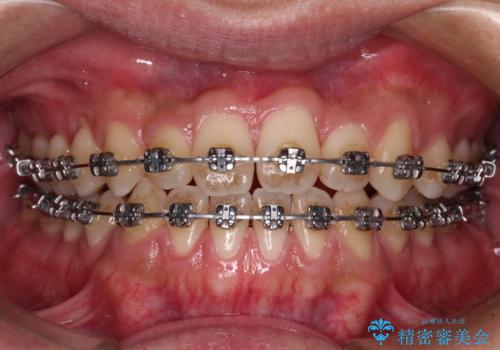

- メタルブラケット

骨格的な左右差も顕著であったため、正中は合わず、上下前歯の一部が接触しない咬み合わせとなることが予想されましたが、正中はもともとのズレが小さかったことから、合わせることができました。

治療期間も10か月間という短期間で終了し、患者様には大変満足していただきました。